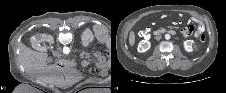

The 2nd CT scan is performed without IV contrast to visualize the trajectory of the probe and ensure that a normal rim of parenchyma is ablated at the deepest margin. Adjustments to the probe should be made at this point. When dealing with larger tumors for example, the tine array may not envelope the entire extent of the tumor and multiple ablations may be required. The probe should cover one aspect of the tumor and the unablated portion can be measured on the CT scan. As the ablated zone from one tine will extend 5 mm, this can be used to plan repositioning, Figure 3.

Immediate post-ablation CT scan and follow up

The final CT scan is performed immediately after ablation with IV contrast (50% of standard dose) to confirm successful ablation. A rim of demarcation seen around the ablation zone signifies a successful treatment. The immediate post-ablation scan is also important to identify complications such as bleeding. Figure 4a represents the tissue changes expected to be seen immediately after ablation.

The American Urological Association guidelines10 recommend obtaining cross sectional imaging with either CT or MRI 3-6 months after ablation and this serves as a baseline to compare future scans. Thereafter, annual abdominal scans are recommended for 5 years. Figure 4b shows the typical "halo" scar expected to be seen several months after ablation. Absence of enhancement on CT or MRI has been shown histologically to be consistent with cancer kill.12 Thus, the urologist should be suspicious of treatment failure or local recurrence when imaging reveals a visually enlarging neoplasm or new nodularity in the ablation zone that enhances with contrast.

Figure 3. A) A bilobed shaped 4 cm right sided tumor is shown. The probe was initially deployed on the inferior aspect of the tumor with tines seen extending into a rim of normal parenchyma. The first ablation was then performed. B) After completion of the first ablation, the probe was repositioned to address the superior aspect of the tumor. After proper probe placement, the second ablation cycle commenced.

Figure 4. A) Immediate post-ablation scan with IV contrast showing a rim of demarcation around the ablation zone. This represents a successful treatment. B) The typical "halo" scar expected to be seen several months after ablation. This particular example is of a left renal mass 12 months after RFA.